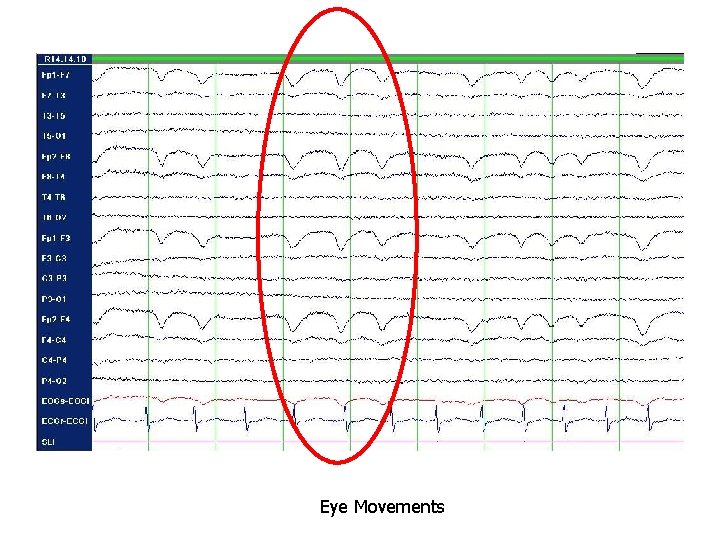

Don’t Forget… 5. Age • Prior to birth, continuous evolution of EEG • Posterior-dominant rhythm by 6 -12 months; alpha frequency by 4 -8 years 6. Artifacts • EKG or pulse • Eye movement • Electrode • Muscle/movement • Electrical • Weird and wonderful

Eye Movements